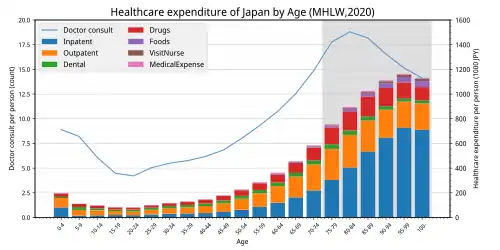

Due to increasing share of the elderly in the population, health care expenditures will continue to grow relative to the economy in coming decades. This has been considered as a negative phenomenon and effective strategies like labour productivity enhancement should be considered to deal with negative consequences of ageing.[124]

Many societies in Western Europe and Japan have ageing populations. While the effects on society are complex, there is a concern about the impact on health care demand. The large number of suggestions in the literature for specific interventions to cope with the expected increase in demand for long-term care in ageing societies can be organized under four headings: improve system performance; redesign service delivery; support informal caregivers; and shift demographic parameters.[132]

However, the annual growth in national health spending is not mainly due to increasing demand from ageing populations, but rather has been driven by rising incomes, costly new medical technology, a shortage of health care workers and informational asymmetries between providers and patients.[133] A number of health problems become more prevalent as people get older. These include mental health problems as well as physical health problems, especially dementia.

It has been estimated that population ageing only explains 0.2 percentage points of the annual growth rate in medical spending of 4.3% since 1970. In addition, certain reforms to the Medicare system in the United States decreased elderly spending on home health care by 12.5% per year between 1996 and 2000.[134]